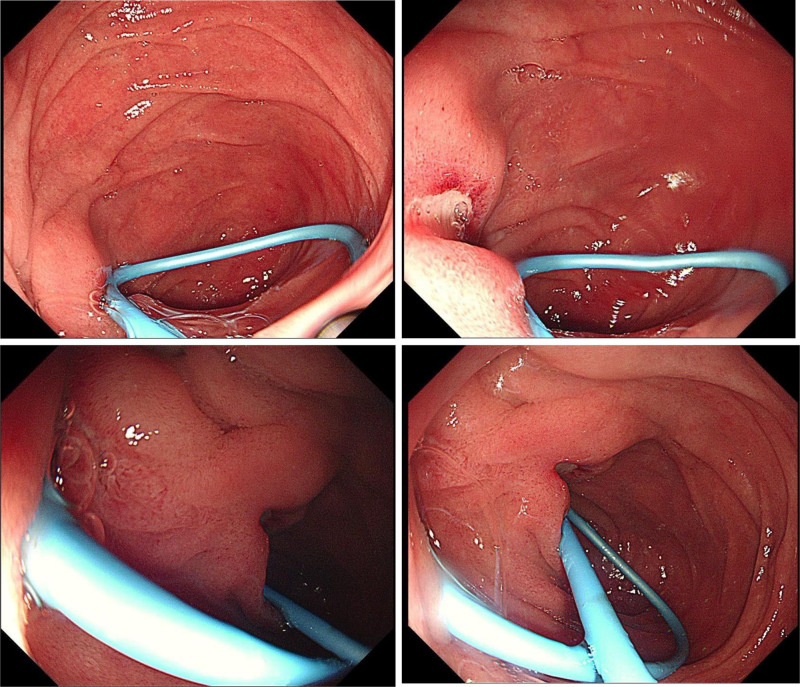

POD 4: Excluding complications such as pancreatitis, cholangitis, and perforation after ERCP, further gastroscopy examination of the duodenum was performed, gastroscopy revealed a fibrin-coated ulcer adjacent to the nasociliary tube in the descending duodenum (Fig. 2). The tube was removed and pain was reduced to a visual analog scale score of 3/10.

In this case, normal amylase and lipase levels at 24 hours and day 4, elevated neutrophil percentages, and abdominal tenderness without rebound pain suggested nonspecific pain. On day 4, gastroscopy revealed an incomplete nasociliary tube causing a friction-induced duodenal ulcer, leading to its removal and pain relief. This case was finally confirmed to have nonspecific abdominal pain caused by a duodenal ulcer through a gastroscopy examination, and follow-up showed pain resolution after 3 days.

By reviewing this case, in which the nasociliary drainage tube is incompletely displaced to the end of the CBD during ERCP, it is recommended that during the ERCP procedure, a curved nasociliary drainage tube be placed along the guidewire under X-ray fluoroscopy to confirm its position in the middle and upper segments of the CBD. This is to avoid placing the tube at the end of the CBD, thereby preventing duodenal ulcers caused by the incomplete displacement of the nasociliary drainage tube. This approach aims to avoid placing the tube at the end of the CBD, thereby preventing duodenal ulcers caused by the incomplete displacement of the nasociliary drainage tube. For predictive nursing care after ERCP, it is crucial to identify risk factors at an early stage and implement corresponding nursing intervention measures promptly. This can help alleviate pain and promote rapid recovery of the patients.